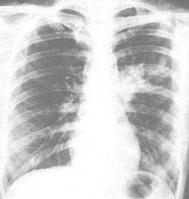

嗜酸性粒細胞2.x線檢查:衣原體肺炎胸片無特異性,多為單側下葉浸潤,表現為節段性肺炎,嚴重者呈廣泛雙側肺炎。沙眼衣原體肺炎胸片顯示雙側廣泛間質和肺泡浸潤,過度充氣征比較常見,偶見大葉實變。

臨床表現:肺炎菌質體侵入呼吸道,首先吸附於黏膜細胞表面,使纖毛活動減弱,並發生淺表炎症,表現為鼻咽炎、喉炎、氣管支氣管炎和間質性肺炎。肺炎菌質體亦可進入血液傳播至其他器官,引起病變。感染後可使人體淋巴細胞致敏,並產生對多個組織器官如血細胞、心、肝、腎、腦、平滑肌等的自身抗體,形成肺外多個組織器官的病變。潛伏期為2~3周。起病緩慢,先表現為感冒和氣管炎。隨之發生畏寒、發熱,體溫升至39℃左右,伴有陣發性劇烈乾咳,咯少量粘液痰,有時痰內帶血。可有頭痛、乏力及食欲不振。肺部體徵常不明顯。X射線胸部透視,肺部可見斑片狀、結節狀或肺門浸潤狀的炎性陰影。發生在肺下葉比較多見,多為單側,少數呈雙側。部分病人伴有胸腔積液。有的病人並不出現症狀,只是在胸部透視時,發現肺部有陰影。須與肺結核鑑別,本病發病2周后肺部陰影可自行消退。本病可出現多種肺外表現,但較少見,表現有溶血性貧血、血小板減少、瀰漫性血管內凝血、結節性紅斑、多形性紅斑、蕁麻疹、關節炎、肌肉痛、胃腸炎、肝炎、心肌炎、心包炎、腦膜炎、腦膜腦炎、脊髓炎、顱神經及周圍神經麻痹、腎炎等。